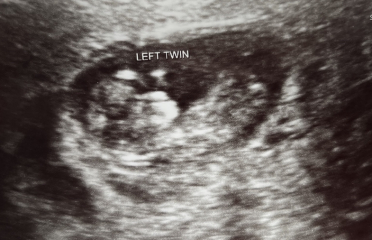

Hi everyone! Sorry I've been quiet on here, half term, a 6 year old and a twin pregnancy to contend with haha! We had another private scan today - I'll be 11 weeks tomorrow and there are two happy healthy wriggly babies in there! Xxx